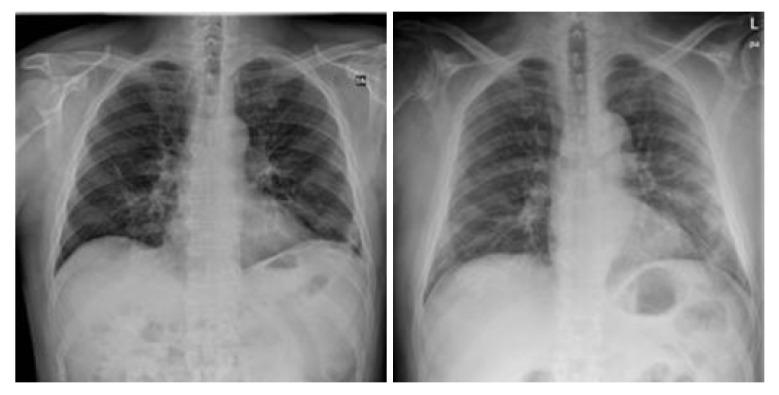

COVID-19,which is caused by the severe acute respiratory syndrome coronavirus 2 (SARS-CoV-2), is one of the worst pandemics in recent history. The identification of patients suspected to be infected with COVID-19 is becoming crucial to reduce its spread. We aimed to validate and test a deep learning model to detect COVID-19 based on chest X-rays. The recent deep convolutional neural network (CNN) RegNetX032 was adapted for detecting COVID-19 from chest X-ray (CXR) images using polymerase chain reaction (RT-PCR) as a reference. The model was customized and trained on five datasets containing more than 15,000 CXR images (including 4148COVID-19-positive cases) and then tested on 321 images (150 COVID-19-positive) from Montfort Hospital. Twenty percent of the data from the five datasets were used as validation data for hyperparameter optimization. Each CXR image was processed by the model to detect COVID-19. Multi-binary classifications were proposed, such as: COVID-19 vs. normal, COVID-19 + pneumonia vs. normal, and pneumonia vs. normal. The performance results were based on the area under the curve (AUC), sensitivity, and specificity. In addition, an explainability model was developed that demonstrated the high performance and high generalization degree of the proposed model in detecting and highlighting the signs of the disease. The fine-tuned RegNetX032 model achieved an overall accuracy score of 96.0%, with an AUC score of 99.1%. The model showed a superior sensitivity of 98.0% in detecting signs from CXR images of COVID-19 patients, and a specificity of 93.0% in detecting healthy CXR images. A second scenario compared COVID-19 + pneumonia vs. normal (healthy X-ray) patients. The model achieved an overall score of 99.1% (AUC) with a sensitivity of 96.0% and specificity of 93.0% on the Montfort dataset. For the validation set, the model achieved an average accuracy of 98.6%, an AUC score of 98.0%, a sensitivity of 98.0%, and a specificity of 96.0% for detection (COVID-19 patients vs. healthy patients). The second scenario compared COVID-19 + pneumonia vs. normal patients. The model achieved an overall score of 98.8% (AUC) with a sensitivity of 97.0% and a specificity of 96.0%. This robust deep learning model demonstrated excellent performance in detecting COVID-19 from chest X-rays. This model could be used to automate the detection of COVID-19 and improve decision making for patient triage and isolation in hospital settings. This could also be used as a complementary aid for radiologists or clinicians when differentiating to make smart decisions.